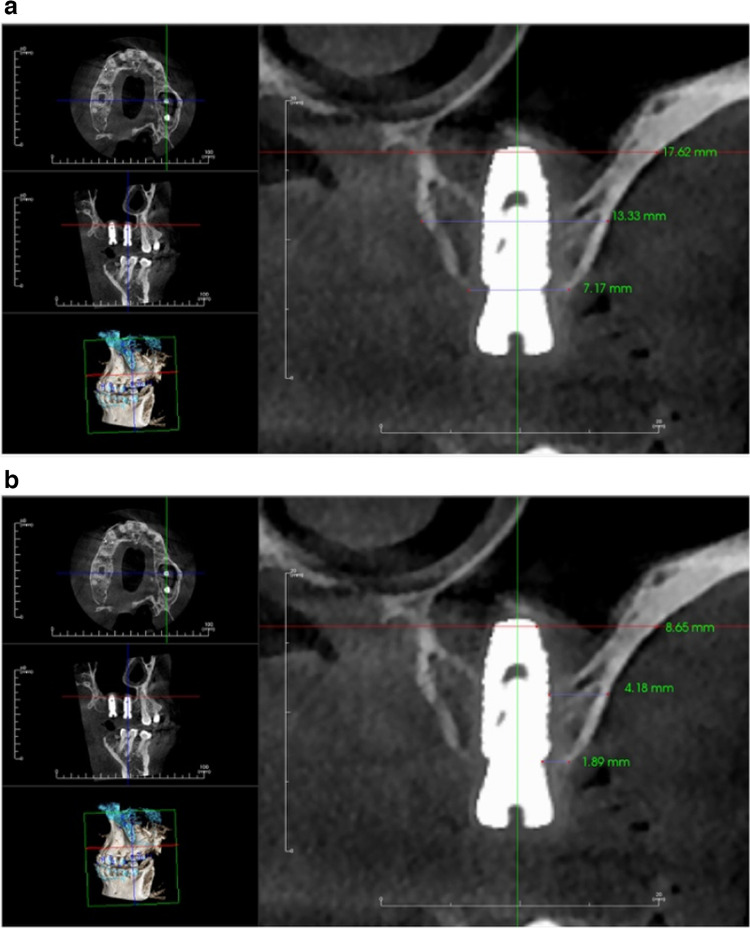

Materials and methods: A total of 30 sinuses with an average residual alveolar bone height ranging from 4-7 mm participated in this randomized controlled clinical trial. Following a closed sinus lift procedure, patients were randomized into two groups: one for the ozone gel recipient group and the other for control group. Cone beam computed tomography was carried out both immediately and four months postoperatively. Radiographic evaluations were performed to assess bone width and labial plate thickness at both crestal and midcrestal levels.

Results: Radiographic analysis revealed that the mean bone width of the control group after four months postoperative was (8.54 ± 1.46 mm) compared to (8.96 ± 1.66 mm) in the study group, which was statistically insignificant (P ≤ .0.05). The mean labial plate of bone thickness value of the control group after four months postoperative was (1.86 ± 0.63 mm) compared to (1.89 ± 0.51 mm) in the study group. Although the bone dimensions in the study group was higher than the control group, it was statistically insignificant (P ≤ .0.05).

Abstract Image